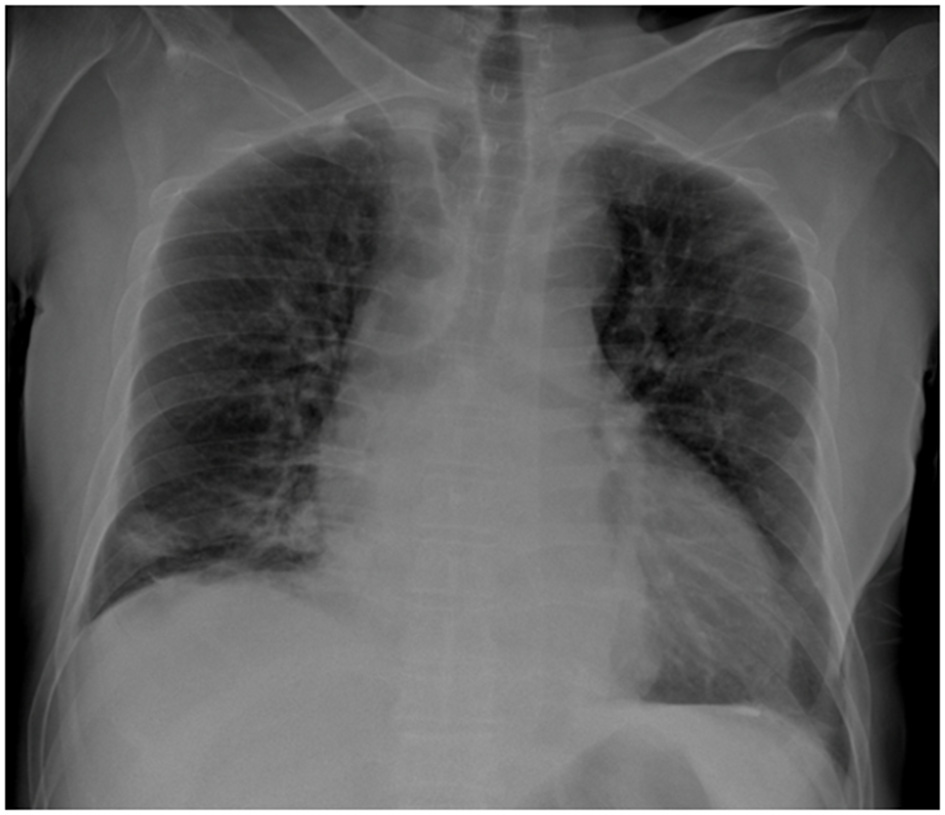

Initial laboratory investigations demonstrated leukocytosis (WBC: 10,770/μl), markedly elevated C-reactive protein (CRP: 358 mg/L), and impaired renal function (eGFR: 57.86 ml/min/1.73 m2). Hepatic and electrolyte panels were within normal limits. Blood cultures were performed. Radiographic imaging of the right knee was unremarkable. Chest radiography revealed right lower lobe consolidation consistent with pneumonia (Figure 1). The patient underwent right knee arthrotomy with intraoperative sampling, and empirical intravenous cefazolin (2 g every 6 h) was initiated.

Figure 1

Posteroanterior chest radiograph demonstrating cardiomegaly and right basal alveolar opacities. The pleural recesses appear clear, with no evidence of pleural or parietal lesions.